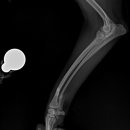

• 24시 에피소드 동물 메디컬 센터 | 만촌동 동물병원 강아지 요골·척골 골절 수술 후기 [24시에피소드동물메디컬센터]

만촌동 동물병원 강아지 요골·척골 골절 수술 후기 [24시에피소드동물메디컬센터] 만촌동 동물병원 ​ 안녕하세요. ​ 풍부한 경험과 따듯한 진료를 바탕으로, 반려동물의 건강하고 행복한 하루하루를 함께 만들어 가는 만촌동 동물병원 24시에피소드동물메디컬센터 입니다. 24시에피소드동물메디컬센터 대구광역시 동구...

에피소드동물메디컬센터(2025-06-26 12:41:00)